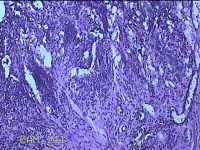

右侧手掌肉芽组织

性别

女

年龄

48岁

临床诊断

手掌开放性损伤

一般病史

右侧手掌肉芽组织增生

标本名称

大体所见

灰白暗红色带皮肤样组织1.3x0.8x0.3cm一块,切面灰白粉红色,质软。